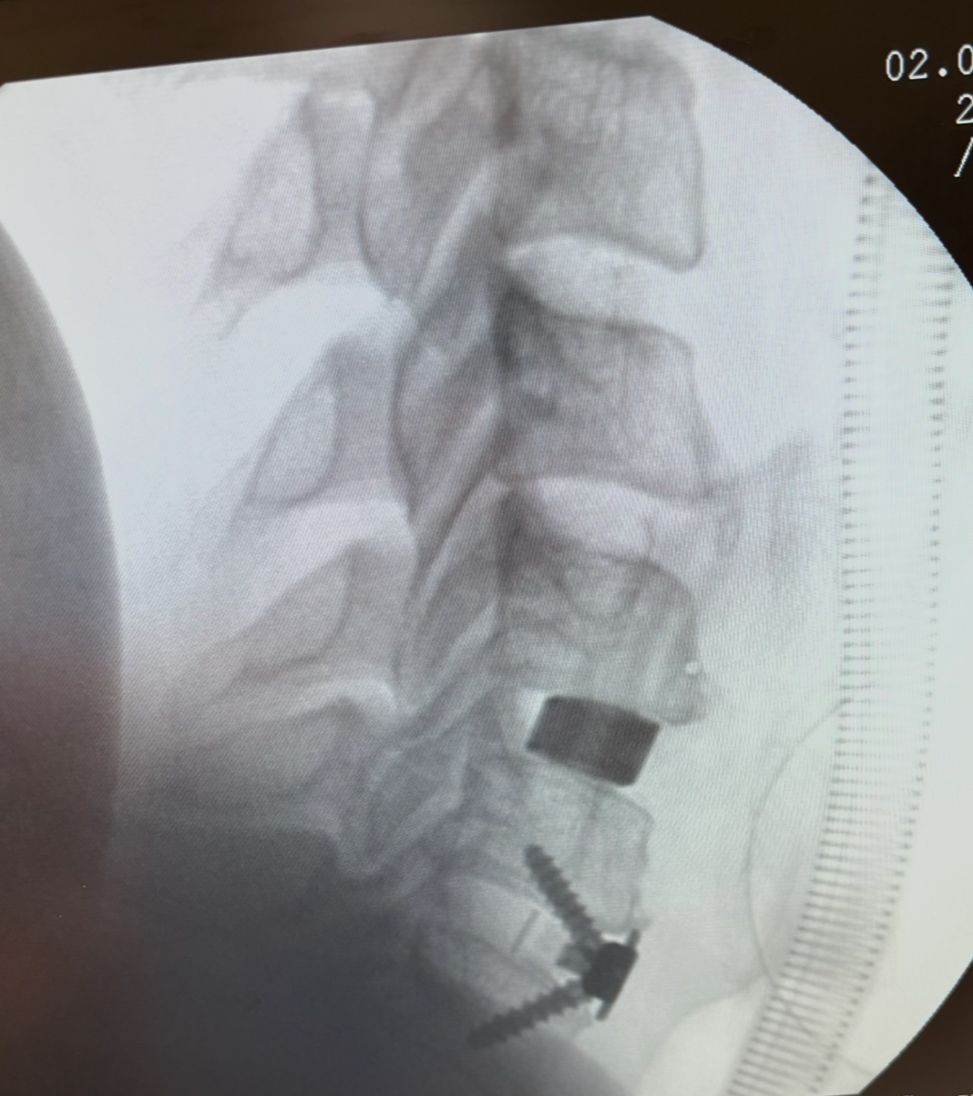

Starszy Asystent w Klinicznym Oddziale Neurochirurgicznym oraz Poradni Neurochirurgii Wojewódzkiego Szpitala Specjalistycznego im. św. Barbary nr 5 w Sosnowcu. Konsultant Kliniki Neurologii Szpitala Klinicznego nr 1 w Zabrzu. Absolwent Wydziału Lekarskiego Śląskiego Uniwersytetu Medycznego w Zabrzu. Staż podyplomowy odbył w latach 2010-2011 w Oddziale Neurochirurgii WSS nr 4 w Bytomiu. W 2018r. złożył egzamin specjalizacyjny po zakończeniu szkolenia w ramach rezydentury w WCM Opole. W 2019 roku uzyskał stopień doktora nauk medycznych. Specjalizuje się w kompleksowym leczeniu schorzeń kręgosłupa (dyskopatia, stenoza kanału kręgowego, kręgozmyk) oraz neuroonkologii. Szczególny zakres działań medycznych to nowoczesne, małoinwazyjne operacje kręgosłupa z wykorzystaniem technik endoskopowych (mikrodiscektomia - implanty rozprężalne), przezskórnych stabilizacji oraz mikrochirurgicznych dekompresji. Wykonuje procedury iniekcyjne; discoGEL, GelSTIX, kriolezje oraz blokady przeciwbólowe kręgosłupa odcinka szyjnego, lędźwiowo-krzyżowego a także stawów krzyżowo-biodrowych, które odgrywają istotną rolę w procesie diagnostyczno-leczniczym wielu zespołów bólowych. Na co dzień przeprowadza operacje w ramach kontraktu z NFZ. Członek Polskiego Towarzystwa Neurochirurgów oraz Polskiego Towarzystwa Chirurgii Kręgosłupa. Uczestnik wielu krajowych i zagranicznych kursów neurochirurgicznych, m.in. w Czechach, Słowacji, Niemczech, Włoszech, Danii, Austrii, Szwajcarii i USA. Autor licznych publikacji naukowych.

Zdjęcia i filmy